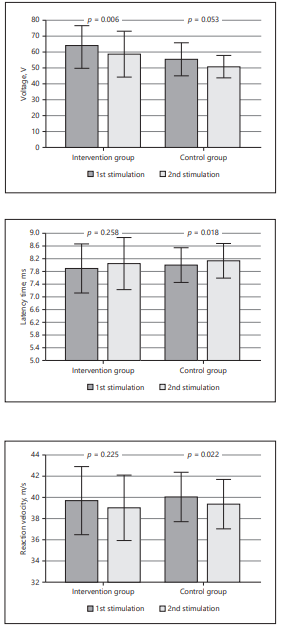

척골신경은 수소음심경에 해당하는 경락과 비슷한 경로를 따릅니다.(팔꿈치신경 안쪽은 수소음심경, 바깥쪽은 수태음폐경이 지나갑니다) 이 연구에서는 네 번째 경혈인 HT4(영도혈)가 사용되었습니다.경혈에는 더 높은 밀도의 자유신경 종말, 촉각과 압력에 대한 더 높은 감각수용체가 있다고 알려져 있습니다.그리고 이러한 구조적 특성으로 말초신경병증에서 유용하게 사용됩니다.침치료의 경우 조직의 혈액관류를 증가시켜 전기생리학적 반응을 증가시킵니다.이 연구에서 침 치료는 척추 신경을 활성화했습니다.그 결과 더 적은 자극으로도 필요한 만큼의 감각을 전달할 수 있었습니다.이는 근육섬유의 동원에 필요한 시간을 감소시키고 반응속도를 증가시키는 것을 의미합니다.따라서 운동신경, 감각신경 기능이 저하되는 포착증후군으로 침 치료는 유용합니다.척추신경 경혈 연구에서 침 치료는 말초신경병증에 효과적으로 사용될 수 있다.정리해 보면 주관 증후군의 원인은 척추 신경의 포착입니다.팔꿈치 신경의 하나인 척추 신경의 포착을 만드는 다양한 원인이 있습니다.이 중 anconeuse pitrochlearis(도르래상 주근)가 척골신경을 누를 수 있습니다.또한 ganglion(결절종)도 척골신경을 누르기도 합니다.4, 5 손가락의 새끼 손가락에서 저리고 악력에 힘이 빠지는 등이 증상으로 나타납니다.경혈 초음파를 이용한 침 치료, 약침 치료가 도움이 될 수 있으며 포착이 심한 경우 논문에 나오는 감압술 등의 수술이 필요할 수 있습니다.